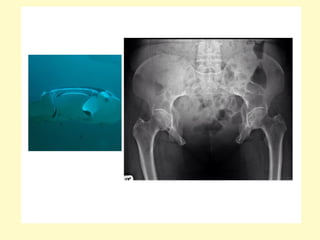

3-Exstrophy :

-There is 2:1 predominance in males

-Also known as ectopia vesicae, refers to a herniation of

the urinary bladder through an anterior abdominal wall

defect

-Failure in development of the mesoderm below the

umbilicus leads to absence of the lower abdominal and

anterior bladder wall

-Imaging findings include a soft-tissue mass extending from

a large infra-umbilical anterior wall defect which may be

close to the umbilical arterial exits, the absence of a

normal urinary bladder and a low-lying umbilical cord

insertion may also indicate the diagnosis

-Failure of the pubic bones to meet in the midline

(widened pubic symphysis), this appearance on AP plain

radiograph of the pelvis (manta ray sign)